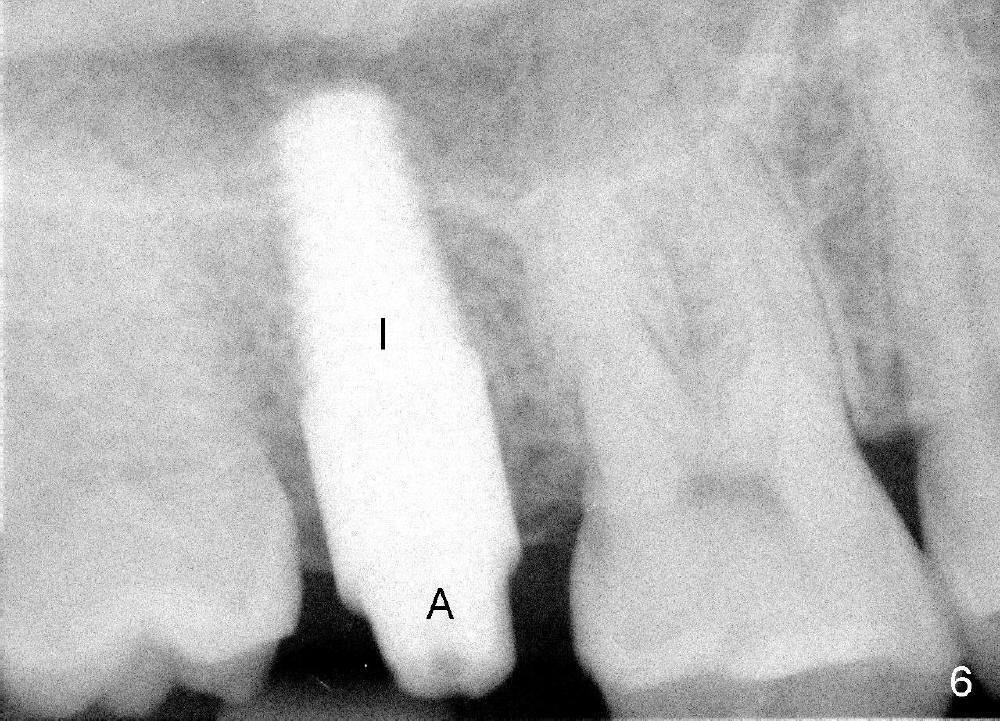

A 42-year-old man is afraid of dentistry. Residual roots of #2 remain untreated for at least 2.5 years (Fig.1). Both the mesiodistal space and the height are limited and unfavorable to restoration (Fig.2,3). Finally he agrees to have treatment, since the tooth #15 is worn so much that it is sensitive to mastication. When the tooth #2 is extracted, the socket is triangular without septum (Fig.4); the bottom of the socket is flat and easy for osteotomy. A 5x17 mm tap has obtained stability once it is placed ~ 14 mm deep (Fig.5). A 5x14 mm implant is placed with insertion torque > 60 Ncm (Fig.6 I), followed by placement of 4x3 mm abutment (A).